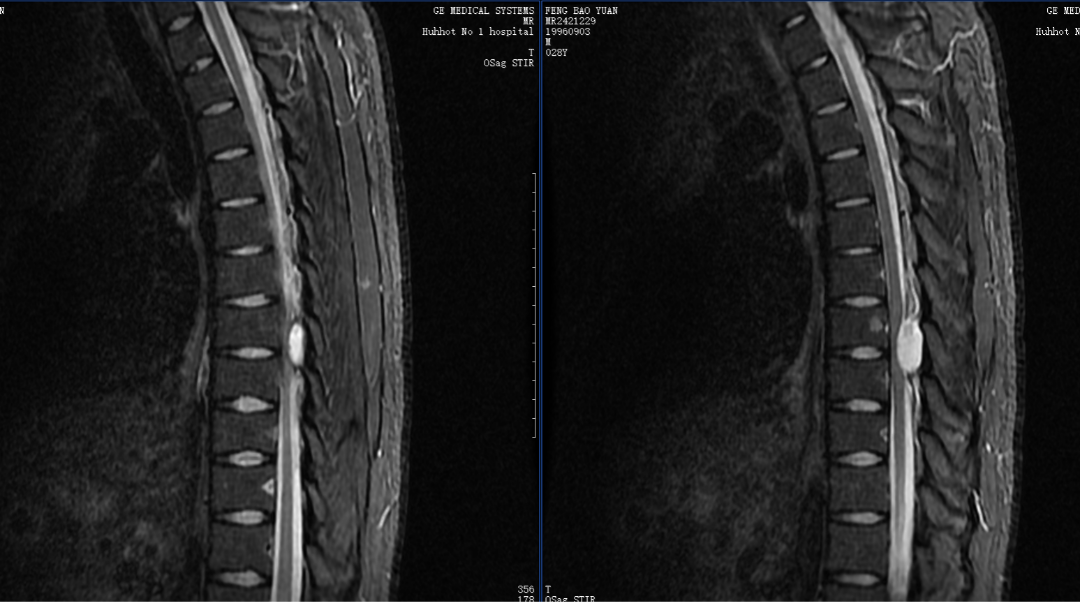

2024年10月24日,第七党支部所辖神经外科收治了一位特殊的患者,患者28岁,男性,因智力残障被遗弃后进入社会福利院,在来院就诊前1周无明显诱因突然出现双下肢活动困难,肌力逐渐下降至0级,福利院及时将患者送来我院就诊,经过完善检查发现患者胸椎7-8水平椎管内占位。第七党支部书记、副主任医师陈波作为患者主治医师考虑到患者智力残障无法配合治疗,以及肿瘤位置的特殊性、手术难度极大等因素,与社会福利院负责人进行充分沟通后,决定在全麻下为患者行手术切除病灶。术前邀请麻醉医学科、疼痛科、脊柱外科进行多学科会诊,共同讨论为患者制定了详细、安全的手术预案,尽可能降低手术风险,减少术后并发症,最大程度改善患者功能。

2024年10月28日,在麻醉科的全力协助下,神经外科主任王伟志、副主任医师陈波为患者进行了胸椎管占位切除术。手术顺利切除病灶,并为患者进行了椎板复位,恢复患者脊椎正常解剖结构。

术后第二天患者下肢肌力较术前改善,手术效果良好。